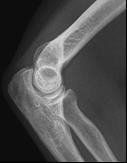

Które zdjęcie RTG stawu łokciowego zostało wykonane w projekcji skośnej w rotacji zewnętrznej?

A. Zdjęcie 1

B. Zdjęcie 2

C. Zdjęcie 3

D. Zdjęcie 4